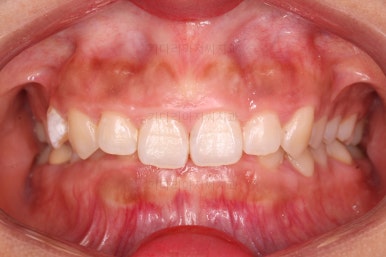

오늘 소개해 드릴 환자분은 아래 앞니가 하나 없는 결손치아, 그로 인해서 윗니 앞니가 뒤로 굽어 들어오는 "옥니", 그로 인해 위아래 앞니가 많이 겹치는 과개교합 및 잇몸웃음(거미스마일)이 나타나는 복합적인 문제가 있는 분이셨습니다.

초진 시 얼굴모습이에요.

아무래도 옥니로 인해서 웃거나 말할 때 앞니가 어두워보이고 잇몸이 많아 보이시네요.

옆라인에서 입은 튀어나온 느낌은 없지만 턱끝만 살짝 볼륨감이 있는 편이었어요.